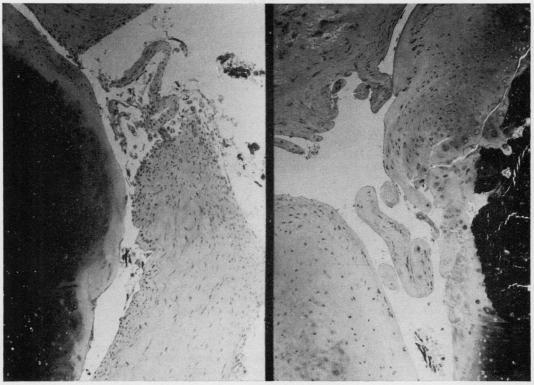

Seventeen rabbits were immunized with complete Freund's adjuvant and bovine serum albumin by the method of Dumonde and Glynn (1962), as modified by Cooke and Jasin (1972). Fifteen weeks after allergic arthritis developed in the knee joint, 8 animals were given an injection of 20 muCi yttrium 90 (90Y) into the left joint cavity; 7 were injected with 400 muCi. The animals were sacrificed at 2, 4, 8, 12, and 16 weeks and at 6 and 12 months after the injection. The right knee joint served as control for assessment of untreated allergic arthritis. Morphological control of the severity of the arthritis was provided by sacrificing 2 uninjected animals 13 weeks after immunization.

按照杜蒙德和格林(1962年)的方法,并经库克和贾辛(1972年)改良,用完全弗氏佐剂和牛血清白蛋白对17只兔子进行免疫。膝关节出现过敏性关节炎15周后,给8只动物的左关节腔内注射20微居里钇90(90Y);7只动物注射400微居里。在注射后2周、4周、8周、12周、16周以及6个月和12个月处死这些动物。右膝关节作为评估未经治疗的过敏性关节炎的对照。在免疫13周后处死2只未注射的动物,以提供关节炎严重程度的形态学对照。